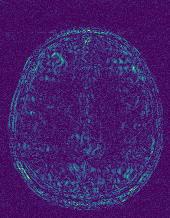

EPN is utilized to provide edge priors for later reconstruction, so the quality of the predicted edges is very important. In Fig. 10, we provide some qualitative results of the predicted edges of EPN on three multi-coil datasets. Among them, the GT edges are extracted using the Sobel operator. As can be seen from the images, our proposed EPN can predict an approximate contour for the overall subject and can reconstruct accurate edges close to the GT edges under two acceleration factors. This fully verifies the effectiveness and excellence of the proposed EPN.

(a)

(b)

(c)

(d)